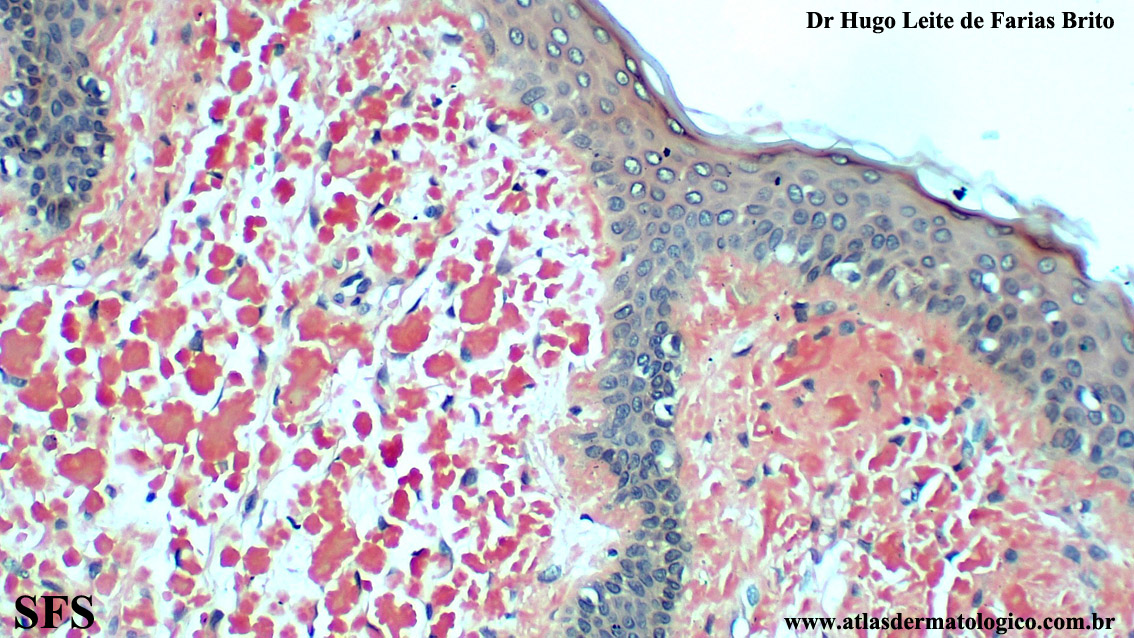

amyloidosis-nodular amyloidosis